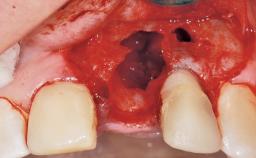

| Placement Protocol | Immediate implant placement |

| Socket Integrity | Damage to one or more bone walls |

| Bone Volume | Damage to one or more socket walls |

| Esthetic Risk | Medium |

| Risk of Complications | High |